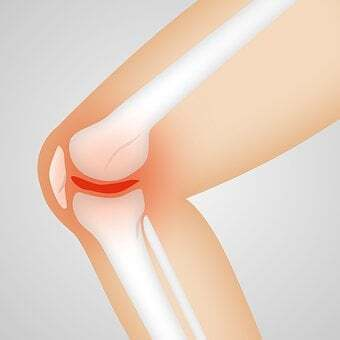

류마티스 관절염은 단순 관절염이 아니라 면역 체계에 이상이 생겨서 나타나는 염증 반응입니다.

시간이 지나면서 관절이 파괴되기 시작하면 작은 관절도 생활에 큰 불편함을 초래하기 시작합니다. 더 나아가 큰 관절로 번지게 되기도 하며 면역 체계 이상에 따른 심각한 합병증 등으로 악화 되기도 합니다.

위의 그림은 류마티스가 순차적으로 진행되는 상태를 나타냅니다. 첫번째 초기단계는 관절낭 안쪽 활막에 염증이 생긴 상태입니다. 중간으로 접어들면서 관절이 붓고 물이 차며 연골이 손상됩니다. 결국 후기로 가면 섬유화가 일어나 뼈와 뼈가 붙어버리는 최악의 경우가 발생하게 됩니다.